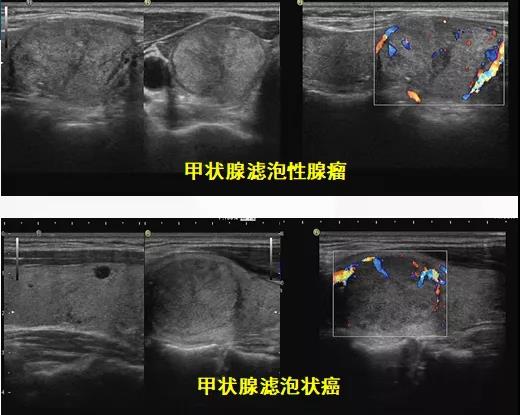

懒癌会复发吗? 甲状腺癌是最为常见的一种内分泌恶性肿瘤,近10年来,其发病率在全球持续快速上涨。约95%的甲状腺癌为分化型甲状腺癌 ( differentiated thyroid cancer,DTC) ,也就是俗称的“懒癌”,主要包括甲状腺乳头状癌( papillary thyroid carcinoma,PTC) ,甲状腺滤泡状癌( follicular thyroid carcinoma,FTC) 和嗜酸细胞癌( Hürthle cell carcinoma,HCC) 。 分化型甲状腺癌(DTC)的长期预后非常好,在10年随访中,成人DTC患者的生存率为92-98%。然而,5%-20%的患者出现局部或区域复发,复发时间从6个月至数十年不等,10-15%的患者继续发展为远处转移。甲状腺床和颈部淋巴结是DTC患者最常见的局部或区域复发部位,而远处转移主要见于肺和骨骼。

术后动态评估主要包括血清学 (TSH、Tg、TgAb等) 及影像学 (颈部超声、DxWBS、CT、MRI等)的规律复查。